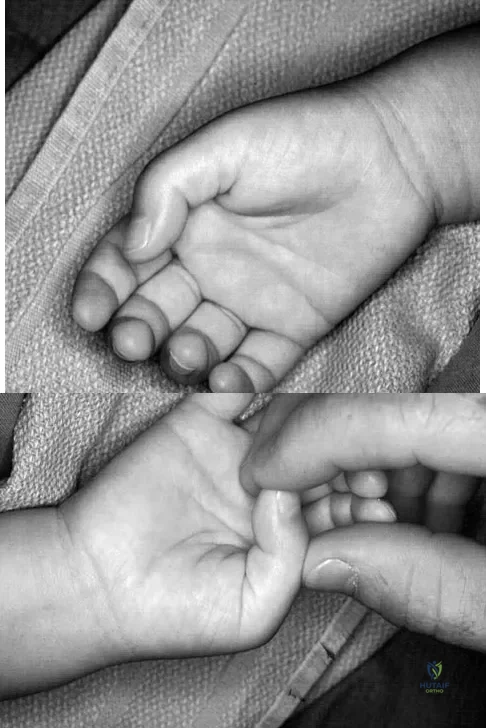

A 6-year-old child has a fixed flexion deformity of the interphalangeal (IP) joint of the right thumb. The thumb is morphologically normal, with a nontender palpable nodule at the base of the metacarpophalangeal joint. Clinical photographs are shown in Figures 42a and 42b. Based on these findings, what is the treatment of choice?

Explanation